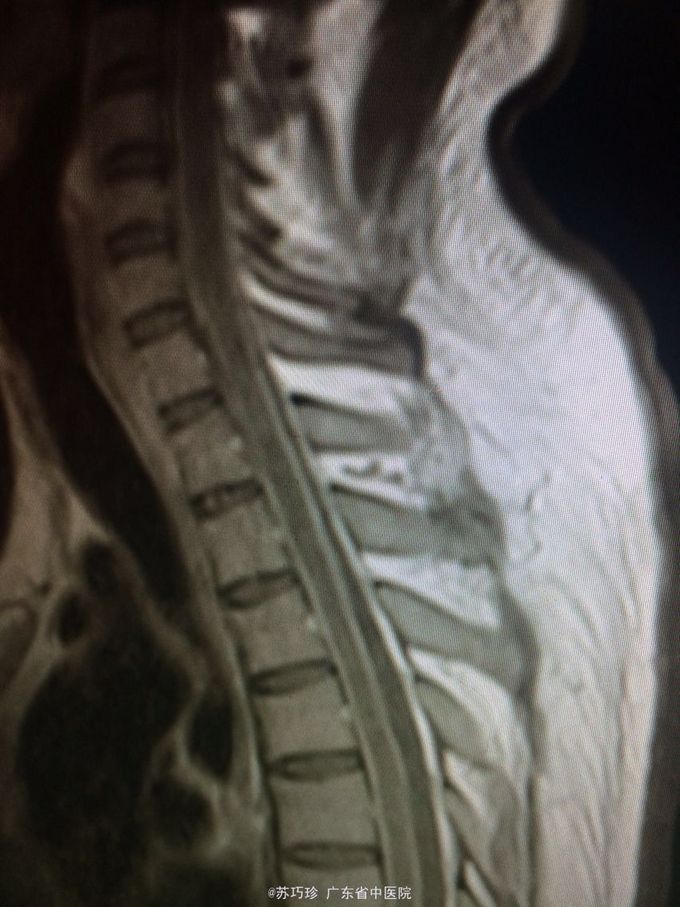

查体:心肺腹(-)。视物重影,右眼外展不到位,T8以下痛、触觉减退,右上肢肌力4级,双下肢肌力0-1级,双下肢肌张力降低,双下肢腱反射消失,腹壁反射消失,颈抵抗约3横指,克氏征(+)。 辅助检查:血常规、肝肾功能及心电图、腹部B超检查未见异常。胸部CT+增强:左肺上叶下舌段慢性炎症;双侧少量胸腔积液,双肺下叶含气不全。头颅+胸椎+腰椎MR平扫+增强:双侧额顶颞枕叶脑沟、双侧侧脑室室管膜、双侧小脑半球软脑膜、脑干软脑膜、颈胸腰段脊髓软脑膜、马尾异常强化影,结合临床考虑炎症性病变;左侧颞叶、左侧丘脑、左侧内囊后肢异常弥散,提示急性脑梗塞灶与感染灶相鉴别,建议复查;脑室系统改变,考虑脑积水;T7/8椎间盘变性,邻近椎体许莫氏结节形成;胸腰椎骨质信号未见异常;骶管囊肿。心脏彩超:EF:64%,主动脉瓣少量返流,左室顺应性减退,少量心包积液。